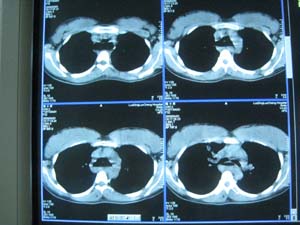

以下是引用卜一在2009-4-1 22:24:00的发言:[br][br] [br] 右肺中叶不张合并感染,建议支气管镜检查排除ca。不能看年轻就不考虑ca,肺ca 也年轻化了。非常支持!. [br] [br]

以下是引用xizhong在2009-4-2 7:32:00的发言:[br]右肺中叶不胀,感染所致(中叶综合症)。

以下是引用当兵的在2009-4-1 23:13:00的发言:[br]右肺中叶不张合并感染,建议支气管镜检查。[br]食管呈大萝卜根,贲门失迟缓,